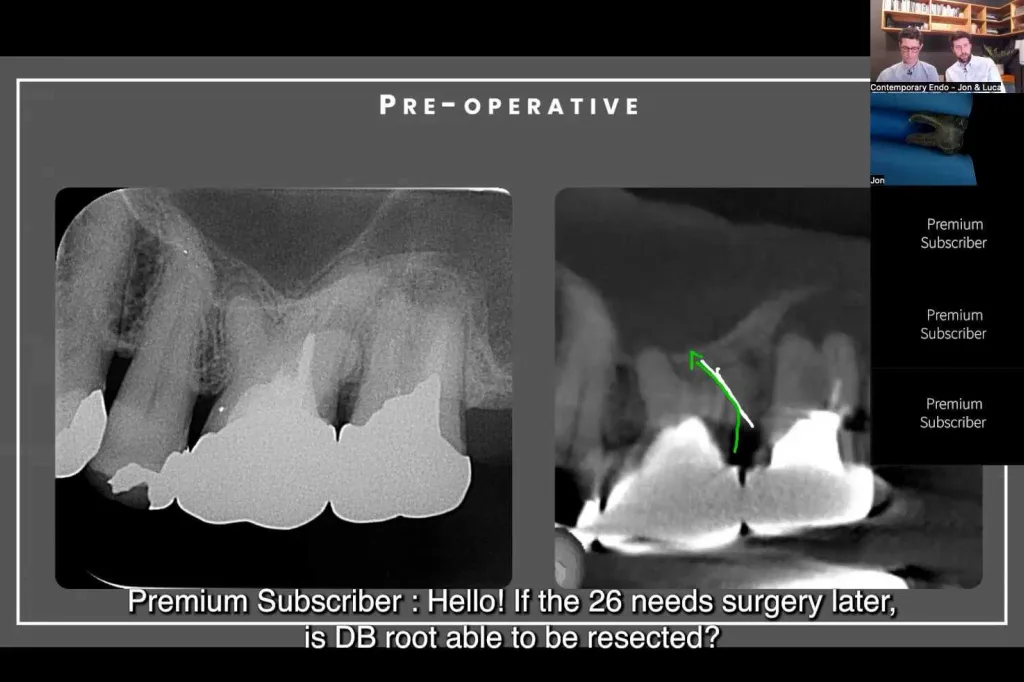

Endodontic case discussions: Navigating MB2s and complex retreatments

Livestream April 7th 2025 -